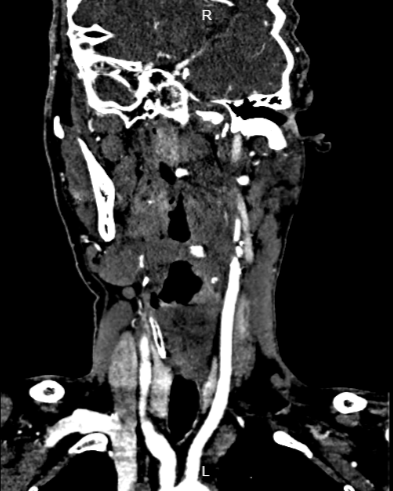

头颈部CTA提示左侧颈内动脉闭塞。

术后第二天影像。